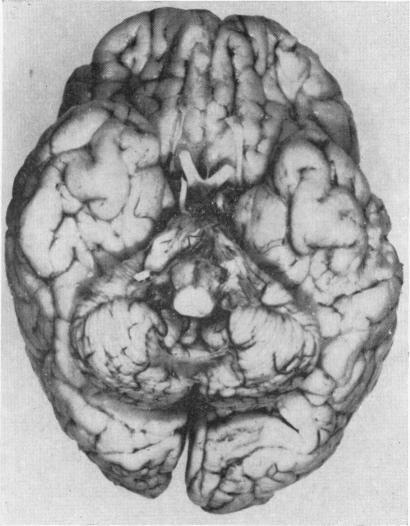

CEREBELLO-THALAMO-SPINAL DEGENERATION IN INFANCY: AN UNUSUAL VARIANT OF WERDNIG-HOFFMANN DISEASE.

Arch Dis Child. 1965 Jun;40(211):302-8. doi: 10.1136/adc.40.211.302.